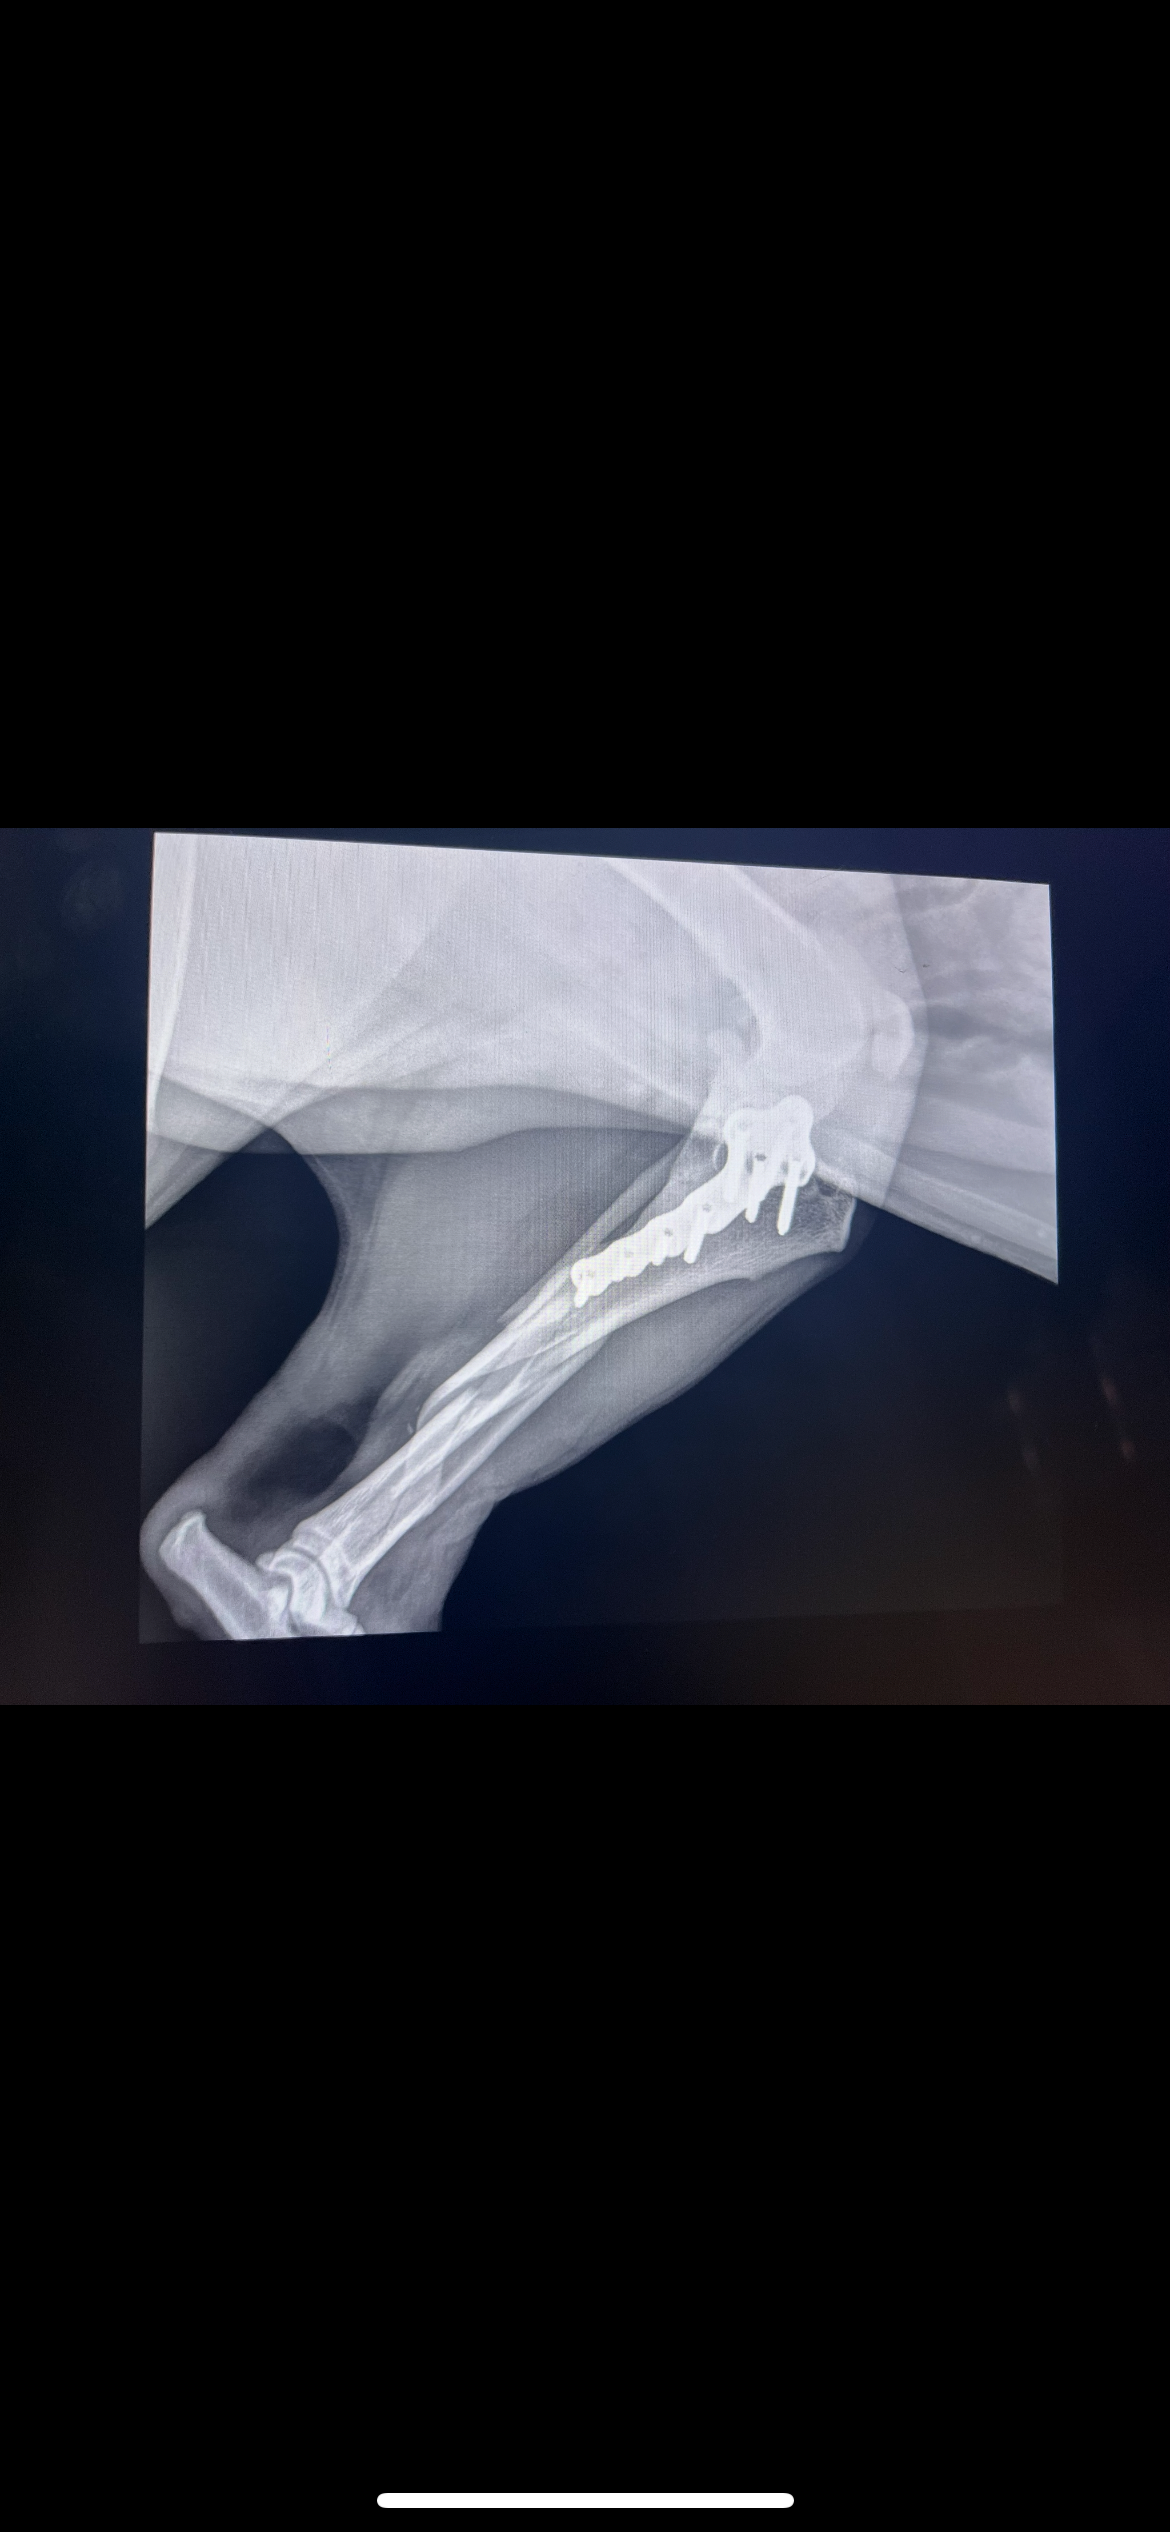

On July 11, Shelby managed to slip out of our yard. Moments later, our worst fears were realized—she was struck by a truck and trailer. The impact left her with a severely broken leg, and we're now faced with a heartbreaking decision: proceed with an expensive surgery or face the possibility of amputation.

We've consulted with veterinarians, and the surgery to repair Shelby's leg is estimated at $5000. This includes the procedure, hospitalization, medications, and follow-up care. Every dollar raised will go directly towards these medical expenses.